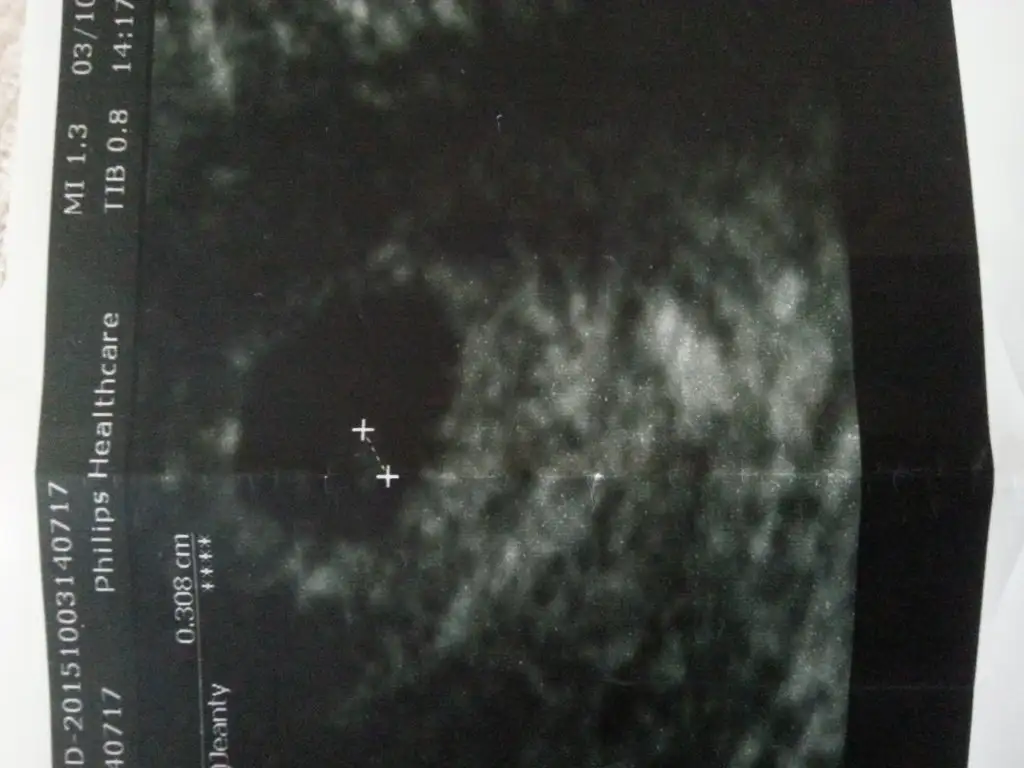

Canım çok sevindim inan inşallah gönlündekidir nub ben anlamadım arkadaşlara göstereyim. Bu arada erkek bebek erken belli olur bende oğlumu 12+4 de dr erkeğe benziyor demişti hatta ben çok aşırı derecede Sevinince geri geldi bak kesin değil ona göre çok kaptırma kendini dedi. Seninki de net emin olmadan söylemek istememiştir. İnşallah hayırlı sağlıklı bir erkek evlattırKızlar günaydın nasılsınız gijnij sana sesleniyorum canım bu bebeğe bi yorum yapsana 11+3 haftalık sizde kızlar anlayan yorum yapabilir mi

Hazal iyiyim canım saol hala bulantılarım devam ediyor halsizlik çok var hep uzanıyorum ve yorgunum belim özellikle çok ağrıyor ben bi kaç gün önce gittim doktora 11+3 haftalıktım doktor cinsiyet için çok erken dedi ben ısrar edince tekrar baktı emin değilim erkeğe benziyor sanki dedi ama bak kesin değil sadece bi tahmin dedi pek sevinemedim niye diye soracaksan kızımdada 11 haftalıkken erkeğe benziyor demişti ama başka bi doktor o yüzden emin olmadan bişey diyemicem canım Allah nasip etsin inşallah burda isteyen herkese çok konuştum sen nasılsın nasıl gidiyor sen ne hissediyorsun ben kızımda kızım olacağını hissediyodum bunda hiç bişey hissedemiyorumSinerjik nasilsin hamileligin nasil geciyor kac hafftalik oldun ben yarin dr a gidiyorum 11+6 olduk cinsiyetle ilgili yorum yaptimi doktor sana?

Iyi diyim iyi olayim canim migde bulantilarim hala devam ediyor yorgunlukta aynen kizlarimin 2 side hasta onlarla ilgileniyorum surekli bugun konrrole gidecegim bakalim ne diycek korkuyorum gitmeye ayrica 2.kizimda kiz olacagini hissettim ilk kizimda kiz istemistim zaten bundada karma karisik duygularim gidip geliyorum ...sen benden ondesin galiba gun olarak 11+7 oldum ben dr erkegemi benzetti hadi insallah canim sevindim insallah oyledir darisi bana ve tum isteyenlere...Hazal iyiyim canım saol hala bulantılarım devam ediyor halsizlik çok var hep uzanıyorum ve yorgunum belim özellikle çok ağrıyor ben bi kaç gün önce gittim doktora 11+3 haftalıktım doktor cinsiyet için çok erken dedi ben ısrar edince tekrar baktı emin değilim erkeğe benziyor sanki dedi ama bak kesin değil sadece bi tahmin dedi pek sevinemedim niye diye soracaksan kızımdada 11 haftalıkken erkeğe benziyor demişti ama başka bi doktor o yüzden emin olmadan bişey diyemicem canım Allah nasip etsin inşallah burda isteyen herkese çok konuştum sen nasılsın nasıl gidiyor sen ne hissediyorsun ben kızımda kızım olacağını hissediyodum bunda hiç bişey hissedemiyorum